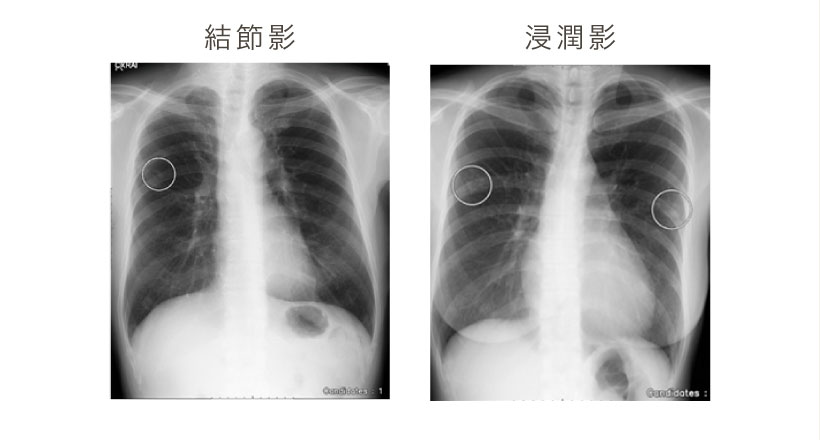

| 胸部レントゲン | ◯ | ◯ | ||||

| 画像診断 | X線検査 | 胸部レントゲン検査 |

| 画像診断 | X線検査 | 胸部レントゲン |

| 胸部レントゲン | 肺がん、肺結核 | 1,500円 |